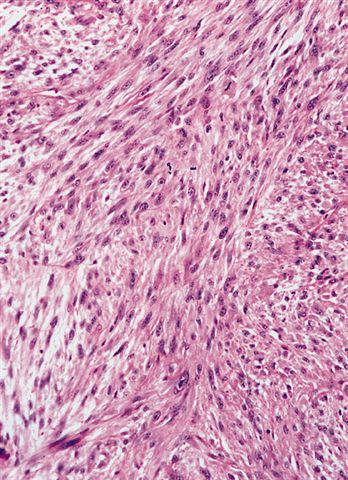

Microscopic (histologic) description

- High grade dedifferentiated liposarcoma

- Well differentiated and dedifferentiated components are often both present and can have abrupt or gradual transitions

- Dedifferentiated component is a cellular and typically a nonlipogenic sarcoma with significant pleomorphism

- Often resembles malignant fibrous histiocytoma (MFH), now referred to as undifferentiated pleomorphic sarcoma (UPS), with short fascicles of pleomorphic spindle cells associated with mixed inflammatory infiltrate

- Can show a peculiar whirling pattern reminiscent of meningothelial structures (Histopathology 1998;33:414, Am J Surg Pathol 1998;22:945)

Microscopic (histologic) images

Contributed by Michael R. Clay, M.D. and AFIP